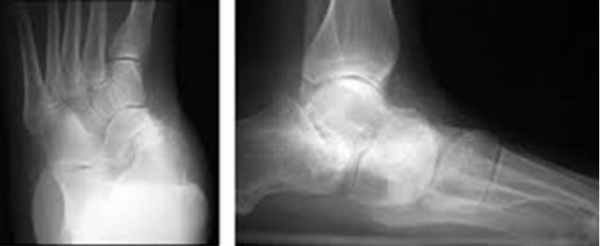

В первую очередь показано выполнение рентгенографии с нагрузкой в прямой и боковой проекции. При этом в прямой проекции выявляется неполное покрытие суставной поверхности головки таранной кости ладьевидной костью, увеличенный угол между таранной костью и первой плюсневой костью (угол Simmon), что встречается со 2 А стадии.

На боковых рентгенограммах определяется увеличенный таранно-плюсневый угол (угол Meary >4° свидетельствует о плоской стопе). Также снижается угол высоты пяточной кости (в норме 17-32°).

На 3-4 стадиях определяются признаки подтаранного артрита, на 4 стадии появляется картина подвывиха таранной кости в голеностопном суставе.